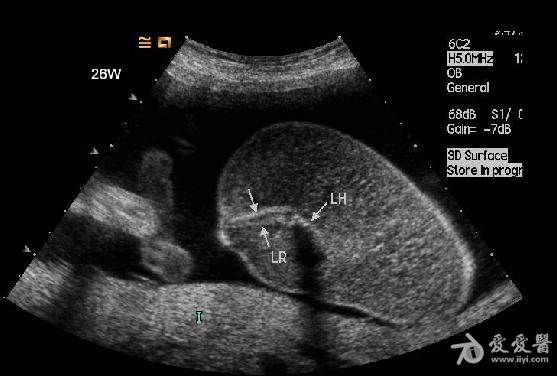

孕妇,26岁。一月前在当地医院超声检查示:双胎妊娠,其中一胎存活(BPD:2.6cm,PL:0.9cm),另一胎死胎并颈部淋巴水囊瘤(BPD:1.9cm,PL:0.9cm)。

双胎中期妊娠:一胎儿发育未见明显异常,另一胎儿无心畸形并全身皮肤高度水肿。

是双胎,其中畸形的那个明显没有上半身及头部,只有下半身和一点点短小的左上肢。

1、双胎中一胎形态、结构发育正常,另一胎出现严重畸形,以上部身体严重畸形为主,可有下部身体如双下肢等结构。

3、上部身体严重畸形,可表现为无头、无双上肢、胸腔发育极差。

5、无心畸胎常有广泛的皮下水肿声像改变,在上部身体常有明显的水囊瘤。